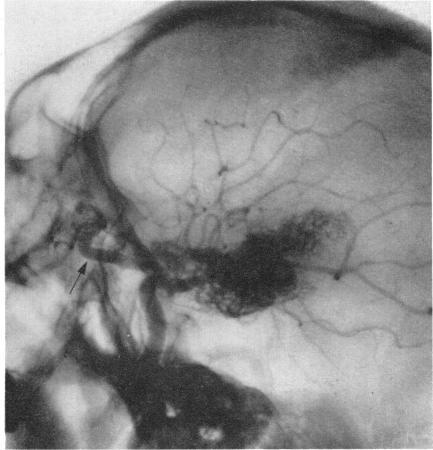

Arteriography and phlebography in the diagnosis of orbital affections.

Bull N Y Acad Med. 1968 Apr;44(4):409-30.